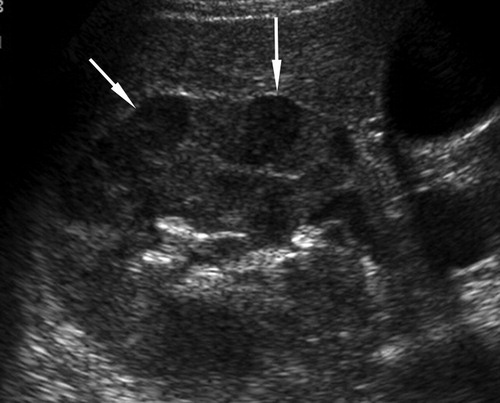

A simple way to grade hydronephrosis is by severity, mild to severe.

Mild

Pelvic fullness with no calyceal dilatation

Moderate

Greater expansion of the renal pelvis and involvement of the calyces

Severe

Further dilatation of the renal collecting system with cortical thinning